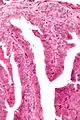

| Micrograph of a papillary hidradenoma with papillary structures; fragmented overlying epidermis is at the top of the image. H&E stain. | |

Microscopic histopathological analyses of papillary hidradenoma tumors typically reveal a nodule in the dermis, i.e. layer of skin between the epidermis and subcutaneous tissue. The tumor consists of complex patterns of interconnecting tubular and papillary (i.e. thin finger-like or frond-like) structures.[19] These structures are lined with glandular epithelial and myoepithelial cells. The glandular epithelial cells appear to be excessively proliferating in the ducts leading to the epidermis and show oxyphilic changes, (i.e. cytoplasm filled with large mitochondria, glycogen, and ribosomes) while the myoepithelial cells often appear clear cell-like, i.e. have uncolored cytoplasm when stained with hematoxylin and eosin.[1] The histopathology of anogenital and ectopic papillary hidradenomas are similar to each other.[7][9][15][18]

Intermediate magnification